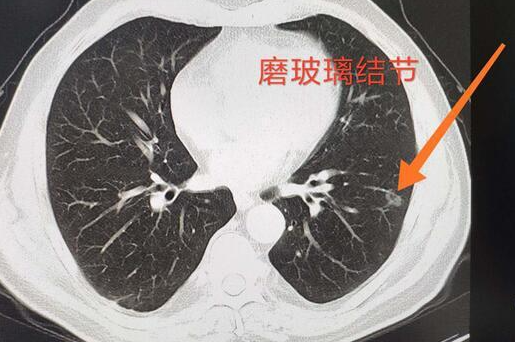

但是在临床工作中,如何去提高磨玻璃结节(GGO)型病变的诊断准确率,尽量避免将良性病变当恶性肿瘤治疗、避免将早期肿瘤当进展期肿瘤治疗以及避免延误早期肺癌的诊治呢?

1、影像学表现为磨玻璃结节最常见的是炎症和早期肺癌,因此GGO常常被认为是早期肺癌的标志。一般来说,持续存在的GGO往往预示着恶性病变,但是少数良性病灶也可能持续存在,比如肺内淋巴结,瘢痕组织;

3、鉴于实性结节中浸润性肺腺癌的比例远大于纯GGO,代表结节密度的CT值可能与病理浸润程度相关。